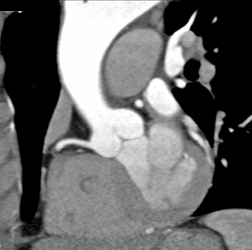

Diagnosis

Stent in LAD and It Is Patent